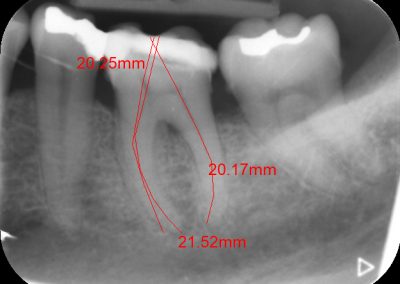

An access cavity is placed on the surface where the patient bites, to reach the root canals of the tooth. Once all the canals are identified, small files are used to remove the infected pulp.

Files of different sizes are used to eliminate bacteria and infection and to shape the canals. The canals are disinfected thoroughly with irrigants and later the canals will be sealed in 3 dimensions with a special medicament called gutta-percha to prevent reinfection of the tooth and the access cavity will be sealed with a temporary filling.

Studies have shown thorough cleaning with instruments, disinfection and sealing the canals contribute to the successful healing of the infection and this success is reported as 95%.